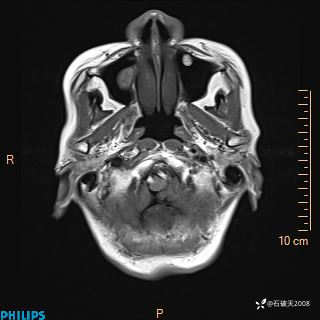

书上说这个肿瘤发生在幕下仅4.09%,你会想到它吗?(病理已公布)

女 86岁 主 诉:乏力1月

现病史:患者1月前活动出现双下肢乏力,无头晕、头痛、恶心、呕吐、肢体活动不利,休息后缓解,间断断发作,症状进行性加重,在家口服药物治疗(具体不详),效差,为进一步诊治,来我院,门诊按“乏力”收住我科,患者自发病以来,神志清,精神稍差,饮食睡眠欠佳,大小便正常,体重未见明显改变。

DWI

ADC